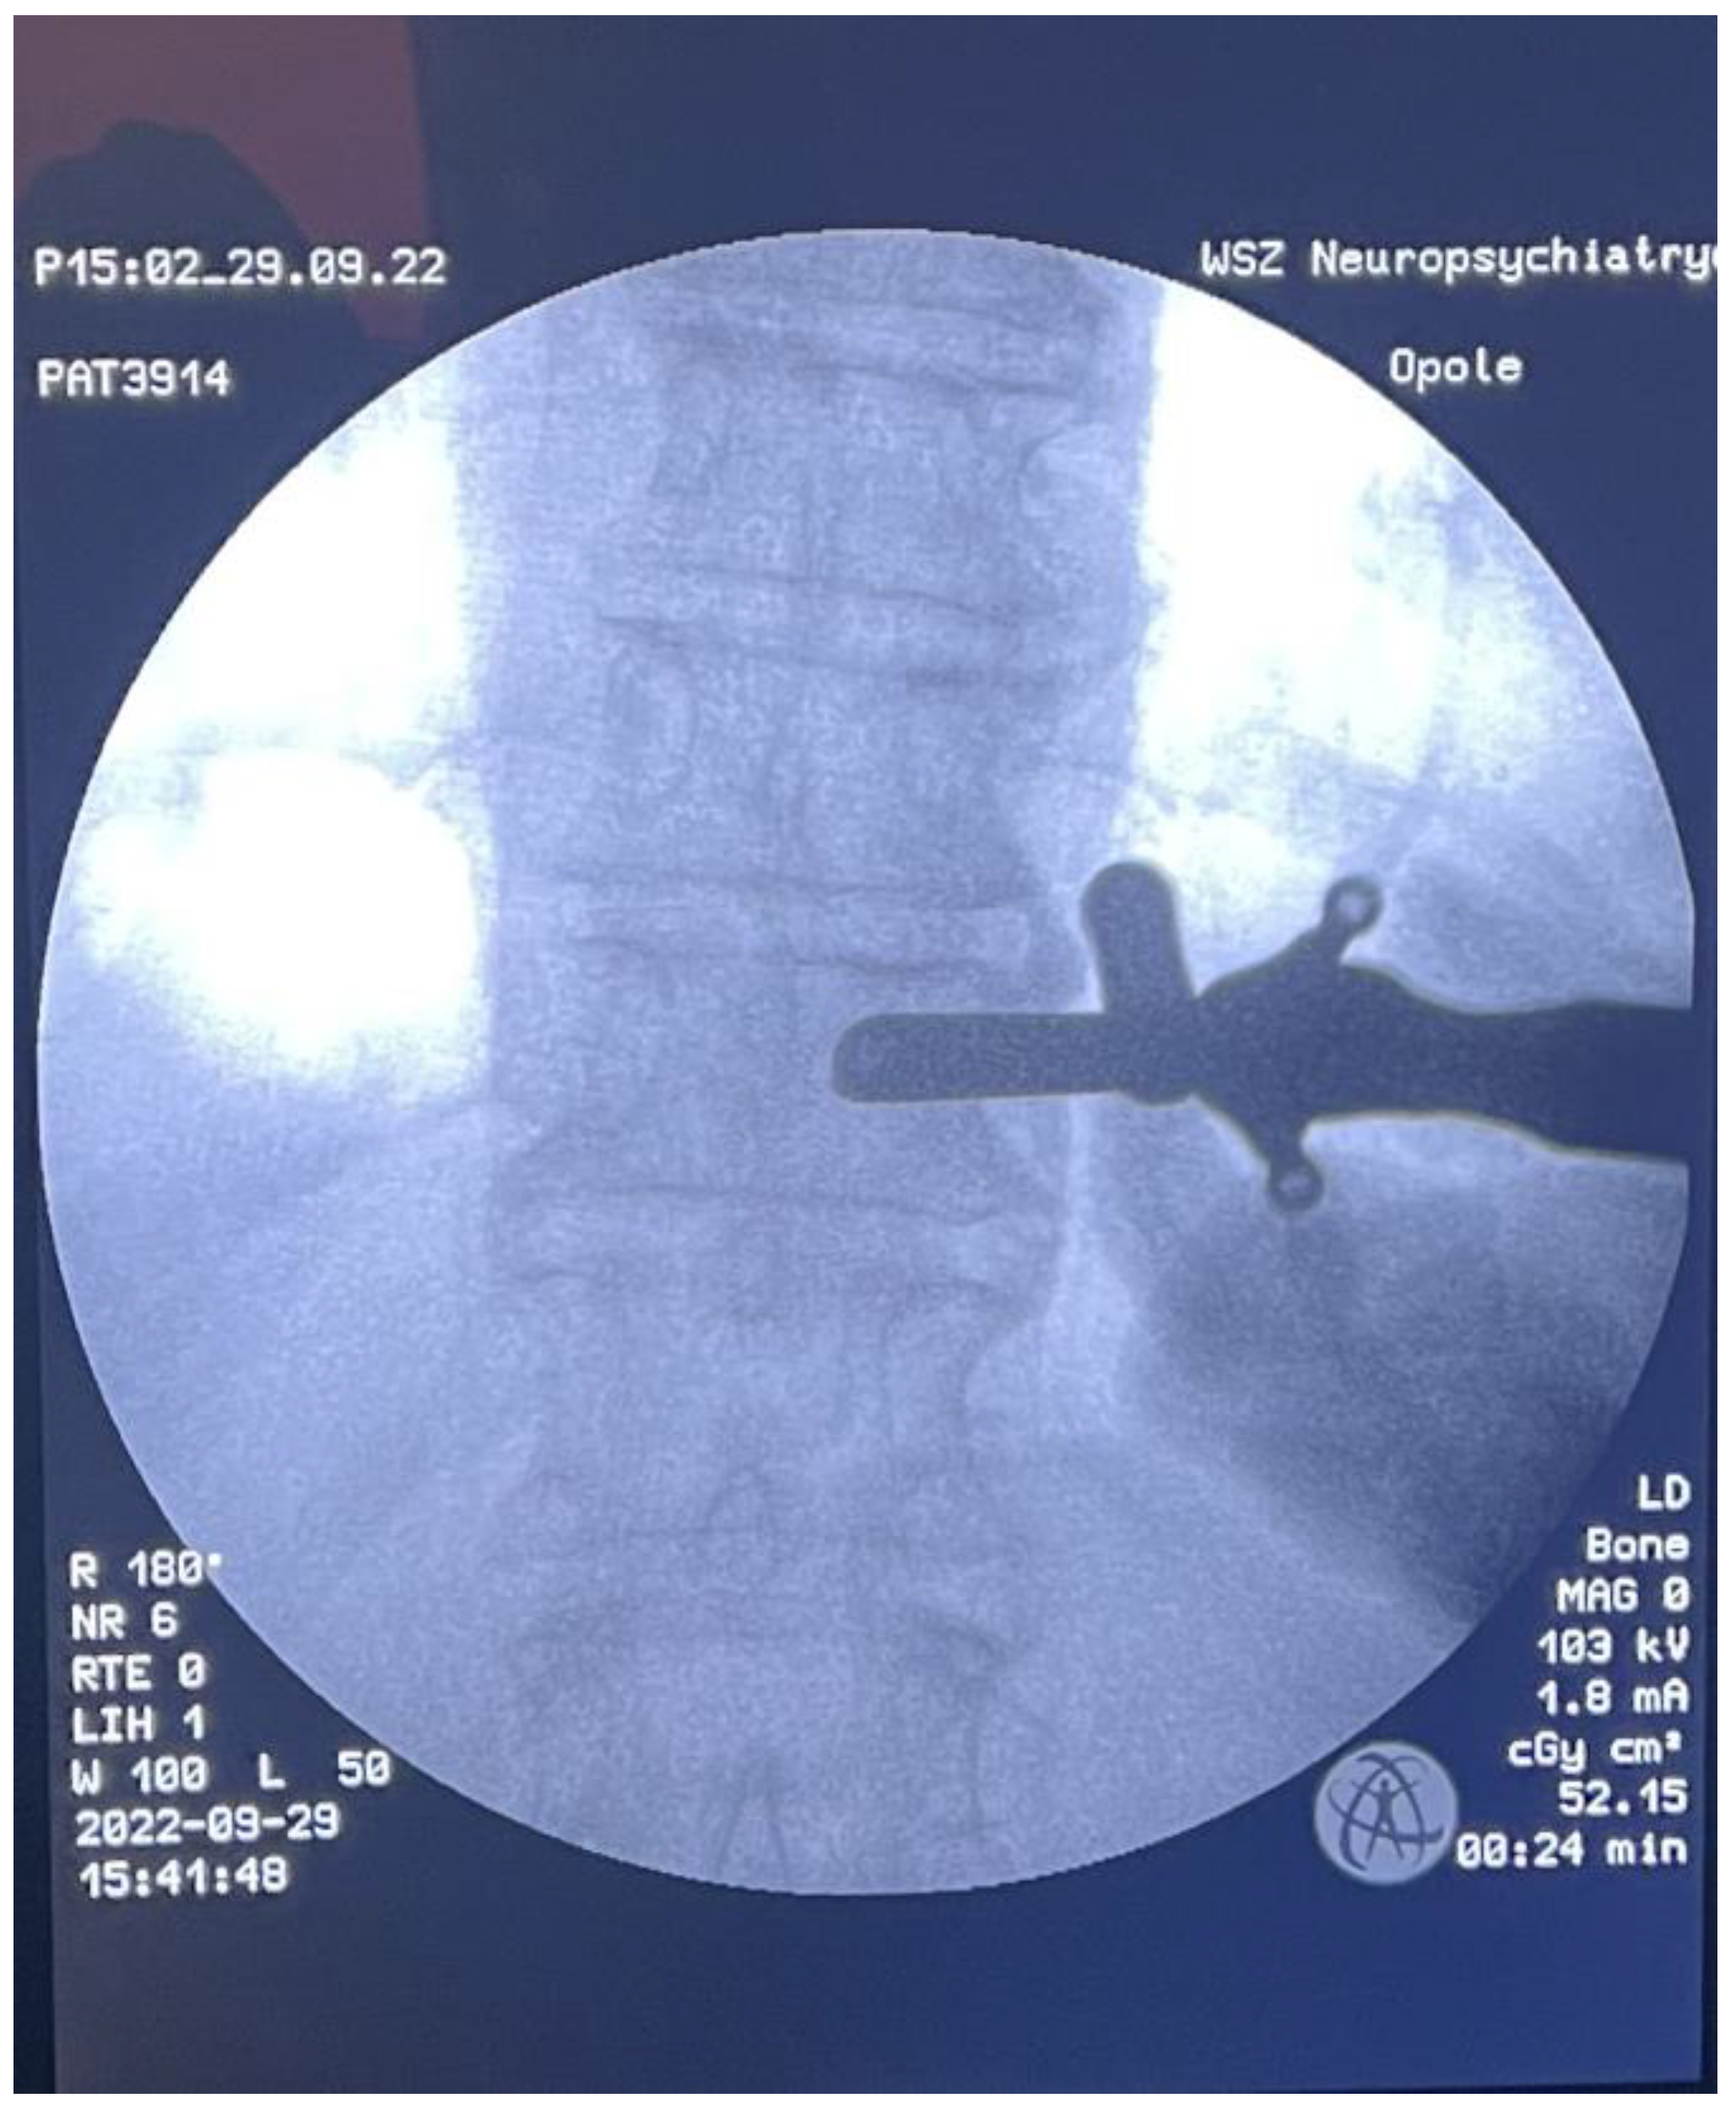

2. Materials and Methods

3. Results